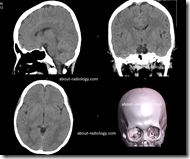

Pemeriksaan Ct Scan Kepala Non Kontras

KRITERIA GAMBAR

• Mencakup gambaran base dan gambaran cerebrum.

• Window / Kernel : Base/ H31s dan Cerebrum/H31s

• Pada kasus trauma : window osteo, kernel H70sharp